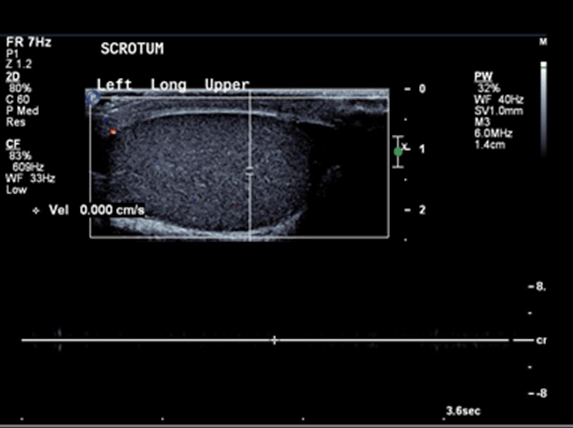

Ultrasound of the scrotum showed polyorchidism with two distinct testes within each hemi-scrotum. The upper left testis measured 3.4x2.5 cm with no Doppler flow to the testis and adjacent hyperemia in the epididymis (Figure 1). The lower left testis measured 1.7x3.3 cm with decreased Doppler flow (Figure 2). The right hemi-scrotum contained two distinct testes measured 2.3x2.6 cm in the right upper testis (Figure 3) and 3.5x3.3 cm in the right lower testis (Figure 4).

Figure 3: Right upper testis with normal Doppler flow and dimensions (2.3x2.6 cm).

The main finding is the presence of a mass with identical echotexture to the ipsilateral testis with the similar flow characteristics to the ipsilateral testis on the color Doppler sonography [5]. In our case, the flow to the left supernumerary testis was absent and the flow to the left ipsilateral testis was also decreased which raised the suspicion of left sided supernumerary testicular torsion.